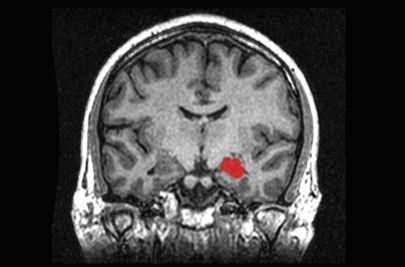

26 – Pedras no cérebro

Um jovem brasileiro, que há 10 anos sofria com dores de cabeça e problemas de visão, descobriu ter um acúmulo de pedras cálcio em seu cérebro. Essas, provavelmente, eram resultado de uma complicação rara causada pela doença celíaca que possuía. Considerada autoimune, ao longo do tempo, a doença pode danificar o revestimento do intestino delgado e impedir que o corpo absorva nutrientes.

De acordo com o relatório do caso, publicado em 2014 pelo New England Journal of Medicine, não ficou claro como a doença resultou em calcificações no cérebro do paciente, mas eles suspeitam que sua baixa capacidade de absorver ferro possa ter desempenhado um papel fundamental.